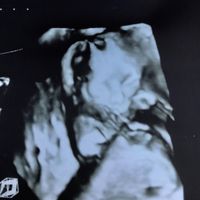

Mamme e future mamme finalmente trovò un po’ di tempo x scrivervi e dirvi ke la mia piccolina dopo l’ultima visita andata un po’ così finalmente è cresciuta, i medicinali fanno il loro effetto e devo...